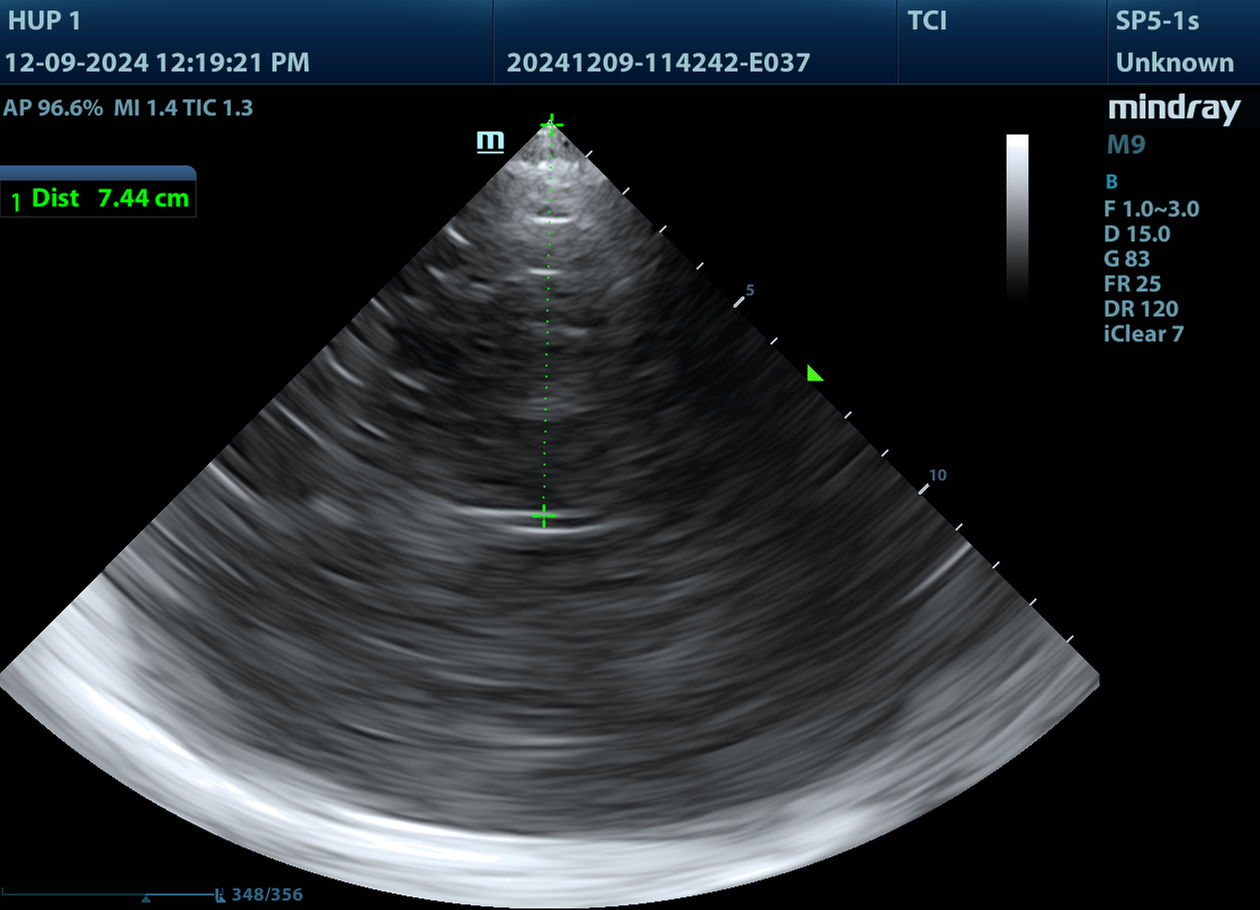

This is the Mesencephalon Plane. But relax, it's just the brainstem, and it will help us find everything else.

Specifically, it's the Midbrain, and this is the view you're most likely to start with if you put the probe down perfectly perpendicular to the temporal bone.

The Midbrain or Mesencephalon looks like the letter "M" turned sideways. Or a Butterfly.

I told you it looks like a butterfly.